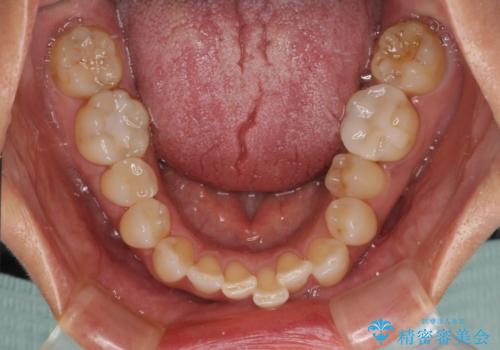

前歯のデコボコとむし歯治療の跡 インビザライン矯正とオールセラミッククラウン治療

- 前歯のセラミッククラウンの縁が見えることが気になってから、デコボコも気になるようになってきたとのことで来院された患者様です。

デコボコの程度は中等度であったため、インビザライン・モデレートパッケージにて歯列を整えることとしました。

奥歯の欠損はインプラント、ブリッジ、入れ歯のどれにすれば良いかを決められず、仕事が非常にお忙しいこともあり、保留としたまま治療を終えることとなりました。

後戻りのリスクがあるため、なるべく早めに欠損補綴治療を開始する予定です。